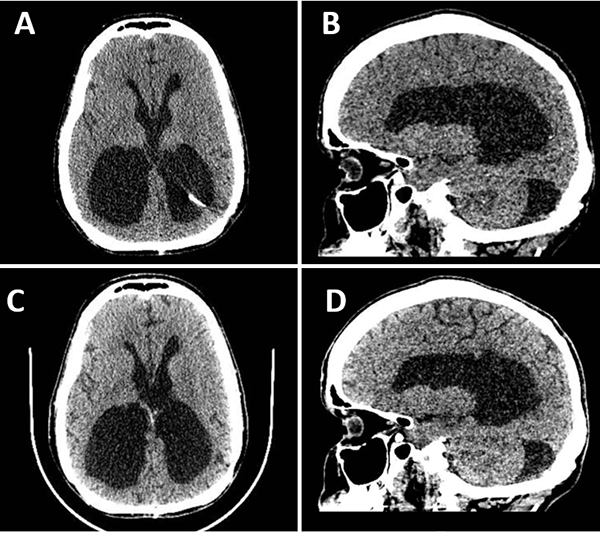

Una vez retirado el segmento migrado, se colocó un nuevo catéter distal en el atrio. Luego del procedimiento, la paciente presentó franca mejoría sintomática con resolución del cuadro de cefalea y Parinaud. Se realizó una tomografía de control a los dos días en donde se corroboró la disminución del volumen del sistema ventricular y fue dada de alta deambulando por sus propios medios. En el control ambulatorio, al mes de la cirugía, se mantuvo asintomática, sin nuevos signos de hidrocefalia ni complicaciones asociadas, con un control imagenológico estable (Figura 4).

Figura 4. A y B. Corte axial y sagital de TC de cerebro en segundo día postoperatorio, evidenciándose franca disminución del volumen del sistema ventricular. C y D. Corte axial y sagital de TC de cerebro control al mes de la cirugía, sin cambios.